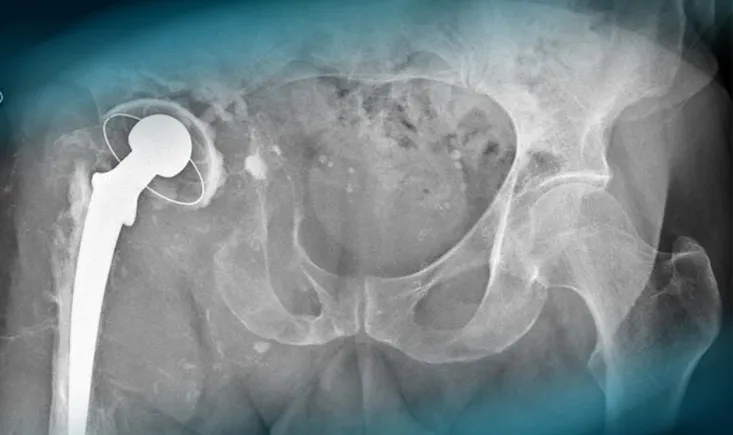

Complex hip revision in a patient with massive massive loss bone stock

A 57-year-old man with a history of hypertension and a right hip replacement in 1993 presents with worsening right hip pain over 10 years. He use…

A 57-year-old man with a history of hypertension and a right…